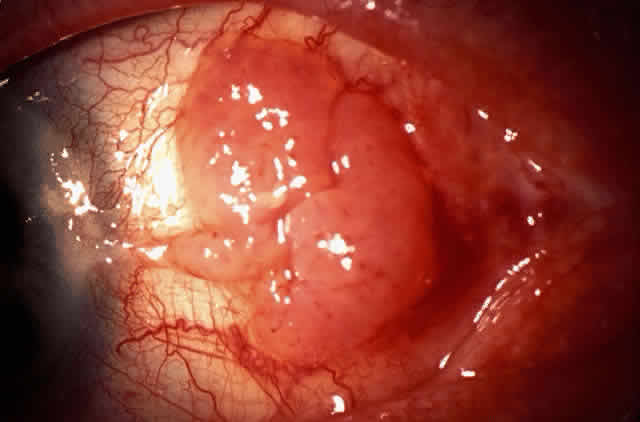

The epithelial dysplastic lesions—conjunctival intraepithelial neoplasia and squamous cell carcinoma—almost always begin at the limbus, most commonly in the interpalpebral zone.57,58 The initial appearance is a gelatinous, gray lesion with some thickening (Fig. 3). There may be increased vascularization. The epithelial changes may extend onto the cornea, causing a hazy, gray appearance. Tumor vascularity lags behind the lead margin of the epithelial change. As the lesions progress from dysplastic to carcinomatous, they become thicker, more vascularized and may show keratinization, giving a leukoplakic appearance (Fig. 4). Lesions confined to the epithelium move freely over the sclera, whereas invasive lesions are fixed to underlying tissue. Occasionally squamous cell carcinomas appear identical to classic papillomas.

Fig. 8. Conjunctival intraepithelial neoplasia. Gray, gelatinous mass is centered at limbus and has prominent vessels. A veil of intraepithelial disease extends laterally across the inferior third of the cornea.

Fig. 9. Squamous cell carcinoma of conjunctiva.